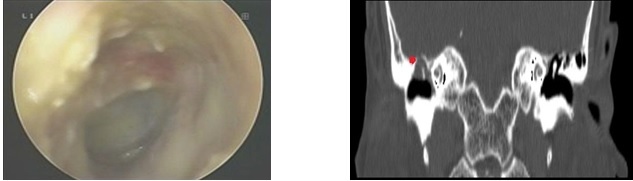

Ảnh: Hình ảnh Nội soi và Chụp CT của bệnh nhân Q

Tại Khoa Tai Mũi Họng – Bệnh viện Đa khoa Bắc Ninh số 2, các bác sĩ vừa điều trị thành công cho một trường hợp viêm tai giữa mạn tính có cholesteatoma với tổn thương nặng. Người bệnh Q. có tiền sử viêm tai giữa phải, chảy dịch tai kéo dài, đã điều trị nội khoa nhiều lần nhưng chỉ giảm triệu chứng tạm thời rồi tái phát. Khi đến khám, người bệnh xuất hiện rõ hơn các biểu hiện như ù tai, nghe kém và tiếp tục chảy dịch tai.

Qua thăm khám lâm sàng, nội soi tai và chụp cắt lớp vi tính tai xương đá, các bác sĩ xác định người bệnh bị viêm tai giữa mạn tính có cholesteatoma tai phải. Bệnh tích đã lan rộng vùng thượng nhĩ, ăn mòn thành sau trên ống tai; đặc biệt, tổn thương xương đã dẫn đến hở màng não – một biến chứng nặng, tiềm ẩn nhiều nguy cơ nguy hiểm.